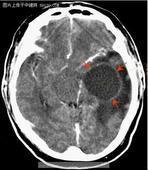

小兒顱內腫瘤

• 小兒顱內腫瘤

628健康網為您分享有關小兒顱內腫瘤的癥狀,小兒顱內腫瘤的治療方法,小兒顱內腫瘤的預防知識,小兒顱內腫瘤的癥狀圖片,小...